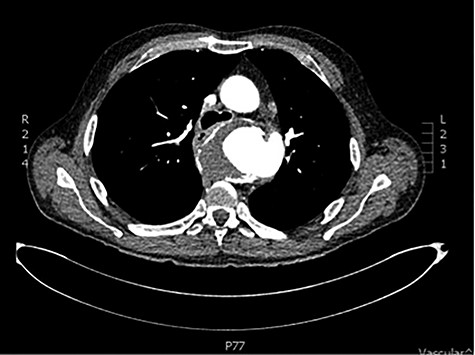

Initial basic investigations demonstrated a fall in his haemoglobin consistent with his history from 14 to 8 g/dl. Oesophago-gastro-duodenoscopy performed at the peripheral hospital was suggestive of a large Mallory–Weiss tear which was injected with adrenaline. Patient also underwent a computer tomography scan which demonstrated a large saccular aneurysm arising from the descending thoracic aorta adjacent to the oesophagus with secondary compression and displacement without any inflammatory or infective features (Fig. 1). CT aortogram did not demonstrate any contrast extravasation or blush into the oesophagus, but a fistula could not be excluded. Upon review of the imaging, it was decided that the patient should be transferred to our tertiary institution for further management with a probable diagnosis of aorto-oesophageal fistula.

CT scan demonstrating close relationship of oesophagus and aortic aneurysm sac.